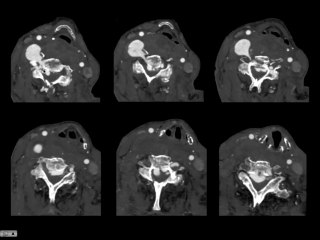

Cette vidéo représente la flexion en 2 temps de l'atlas au cours d'une rotation du rachis cervical supérieur.